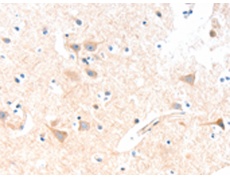

ELISA, IHC |

IHC positive control: |

Human brain |

IHC Recommend dilution: |

15-50 |